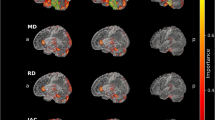

Finally, we explored whether FA-related degradations in the CC were associated with microstructural degradation in the rest of the brain over the 24-month period. There were widespread significant changes in both FA and MD associated with callosal FA change, as shown in Fig. 5, including many regions implicated in PD, such as the cerebellum, thalamus, and hippocampus.

Finally, to explore the potential impact of early CC degradation on the rest of the brain, we examined how changes in FA over 24 months in the full callosal ROI correlate with voxel-wise FA and MD changes in the rest of the brain. First, baseline versus 24-month microstructural alteration FA and MD maps were created using the ImCalc function, using the FA and MD images of all 61 individuals. For FA, the difference maps were created by subtracting each individual’s 24-month time-point images from their baseline images. For MD, the difference maps were created by subtracting each individual’s baseline images from their 24-month images. That is, positive values in both difference maps indicate microstructural decline over time. Second, the ROI callosal regressor was calculated by subtracting the average 24-month full CC FA from the baseline CC FA for each individual subject. Third, the FA/MD difference maps together with the callosal regressor were used in the SPM12 voxel-wise whole-brain multiple-regression analysis, with age, gender, and years of education as covariates. The resulting regression maps were thresholded at p < 0.001 and k > 9, with clusters deemed significant if they survived FDR correction of p < 0.05.